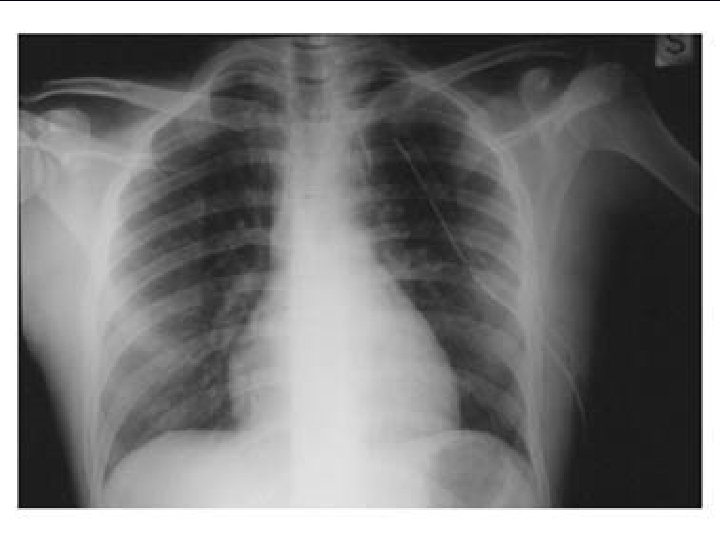

IL PNX IN RADIOLOGIA